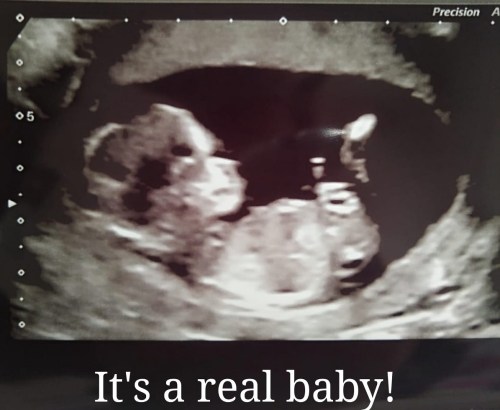

its a real baby 🙂

its a real baby